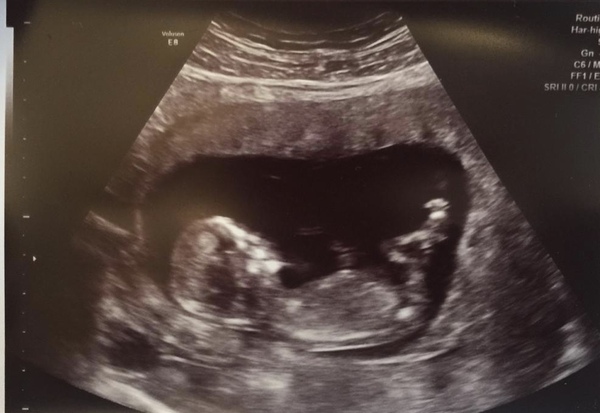

Bumpingalong84 · 22/11/2019 20:47

It would help if I posted the scans 🙈

GinUnicorn · 22/11/2019 20:48

@november90

It’s here but I can’t see a damn thing!!